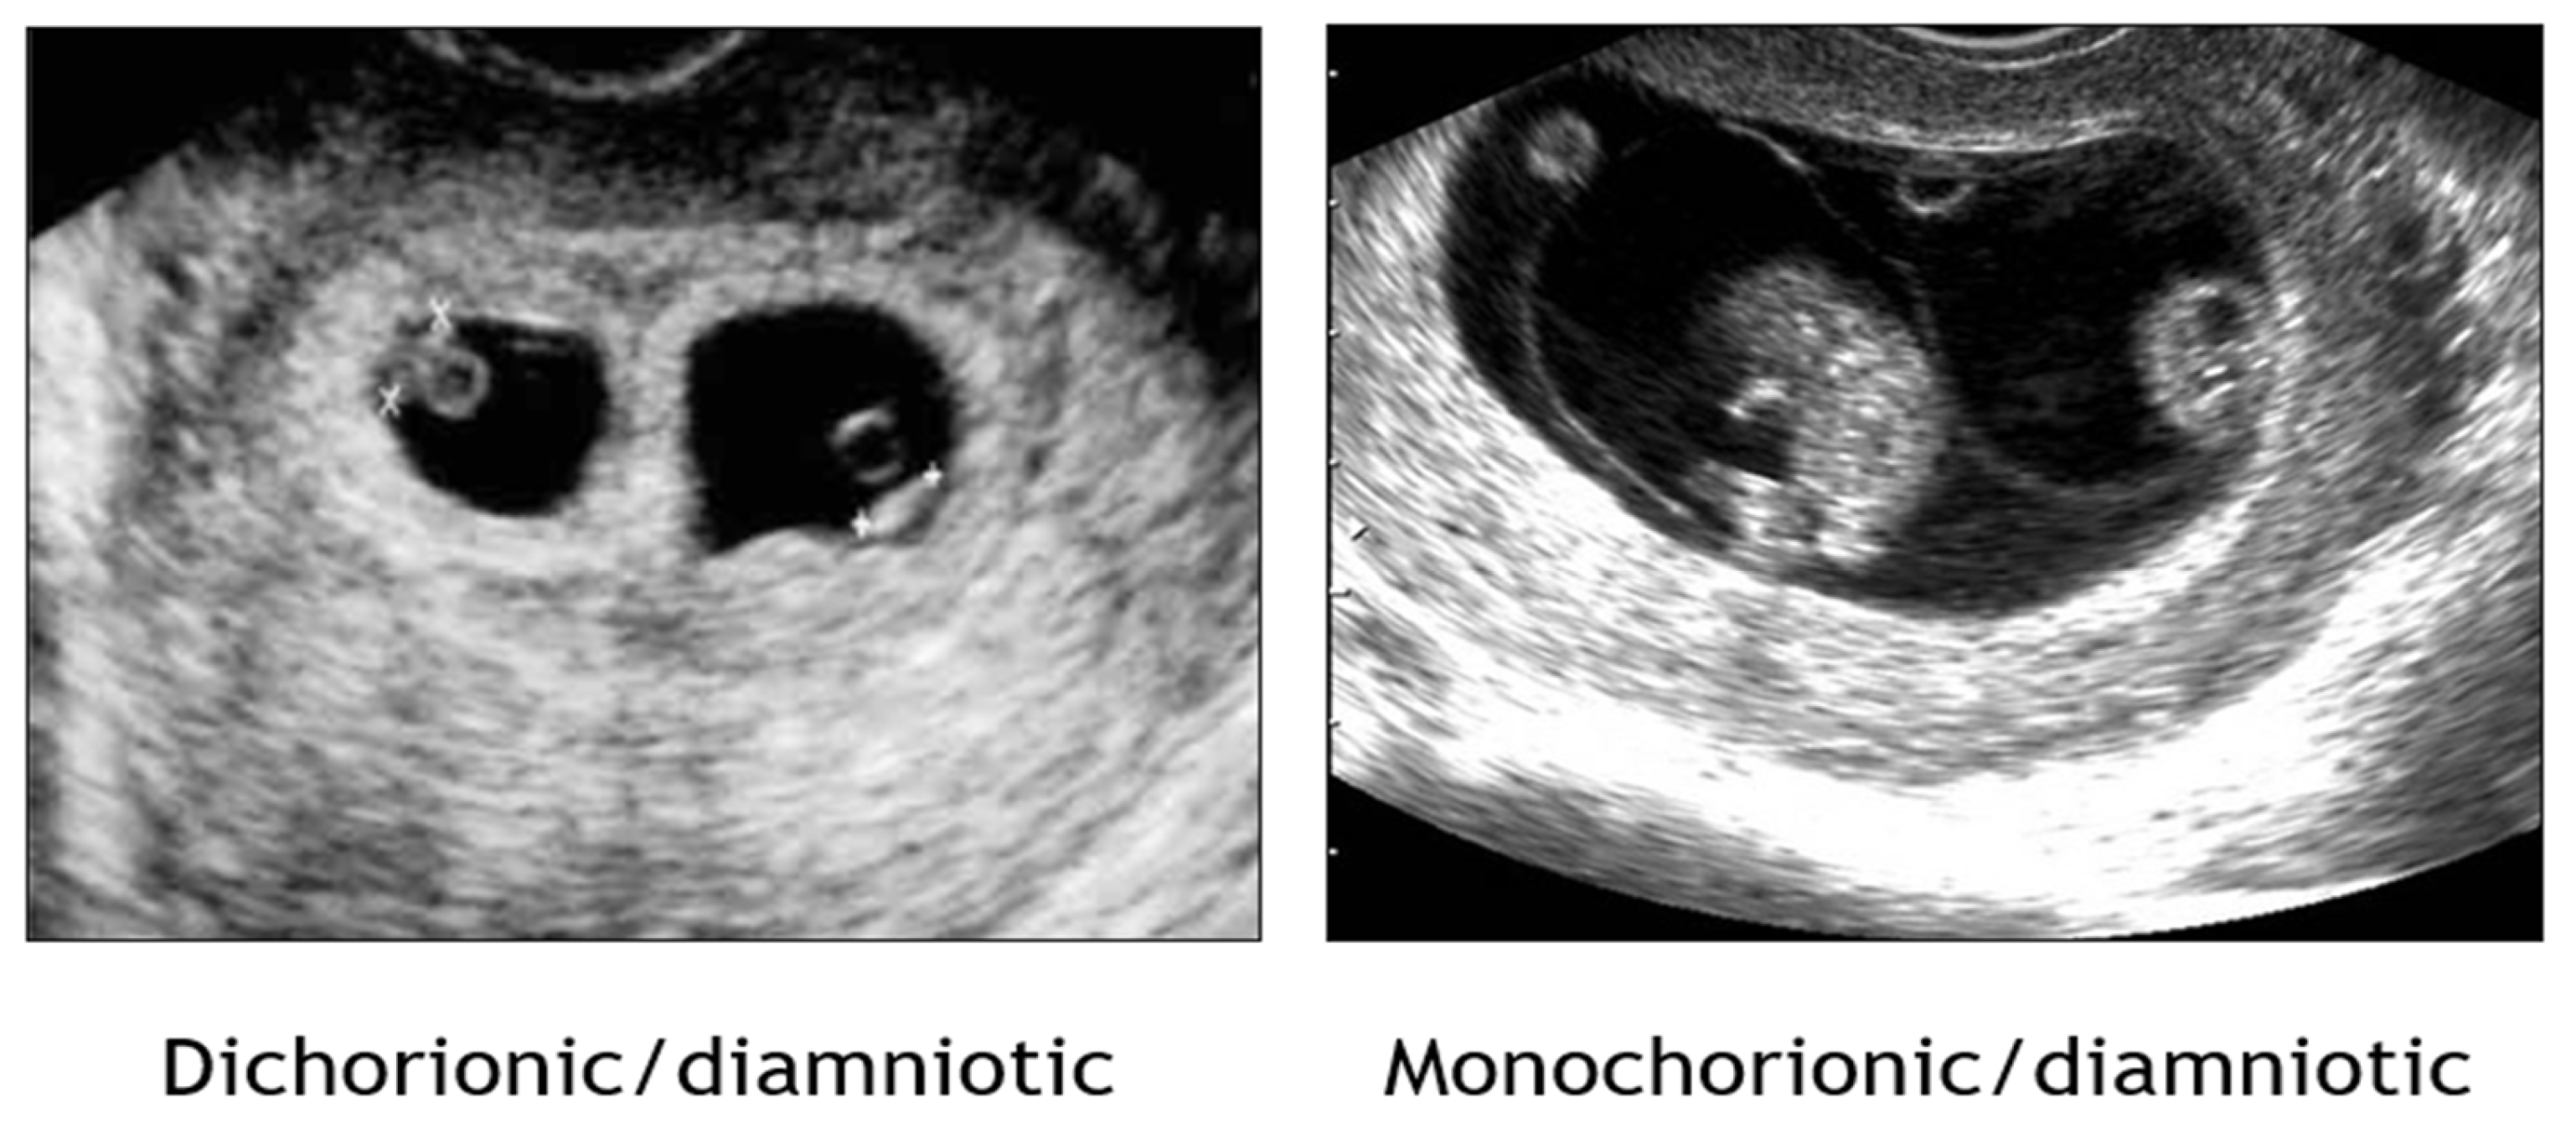

1.2. Establishment of Chorionicity and Amnionicity

- First trimester ultrasound remains paramount in discerning chorionicity in twins and high order multiple gestations [Level II-2A; B].